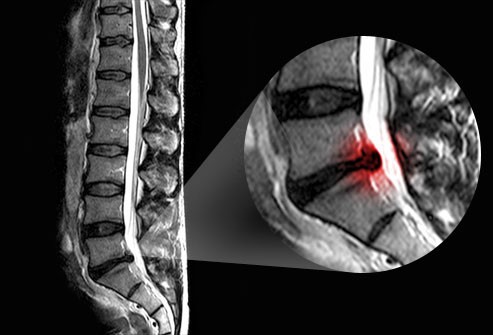

در این روش، بیمار با انجام یک سری حرکات مشخص و تکراری، به بدن اجازه میدهد،پوسچر خود را اصلاح کند. این تمرینات بیشتر شامل حرکات اکستنشن (باز شدن کمر به عقب) هستند و به کاهش التهاب ریشههای عصبی، رفع دردهای تیرکشنده به پا و برگرداندن درد از اندامها به ناحیه اصلی (centralization) کمک میکنند؛ یعنی درد از ساق، ران یا باسن دوباره به کمر برمیگردد که نشانهی بهبود واقعی است.

وقتی دیسک یا ریشه عصبی تحریک میشود، درد از کمر به باسن، ران یا ساق پا منتشر میشود.

تمرینات اکستنشن مککنزی، با تغییر توزیع فشار داخل دیسک، کمک میکنند دردِ پخششده به سمت کمر برگردد. این روند نشانهی بهبود است.

حرکت اکستنشن باعث میشود قسمت بیرونزده دیسک به مرکز نزدیکتر شود و فشار از روی عصب برداشته شود.

چون حرکات اکستنشن فشار داخل دیسک را کاهش میدهد و درد را به مرکز (کمر) برمیگرداند.

حرکات اکستنشن کمک میکنند قسمت برجسته دیسک به مرکز برگردد و فشار از روی عصب برداشته شود.